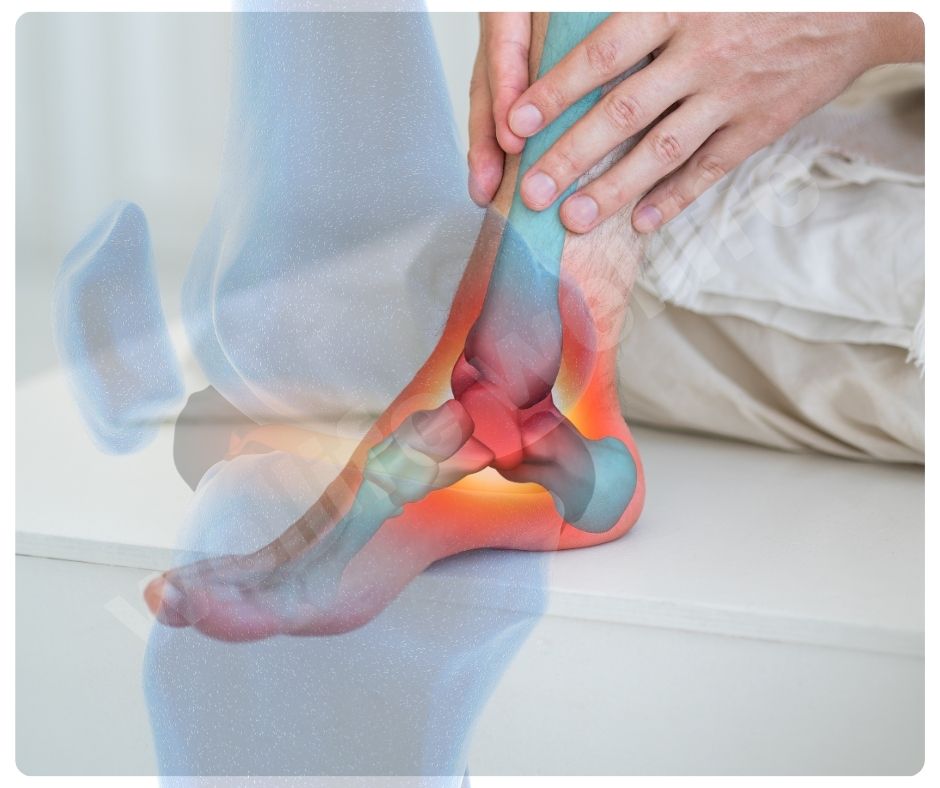

콘드로이친 효능 중 가장 대표적인 것은 골관절염(Osteoarthritis) 완화입니다. 골관절염은 연골이 닳아 없어지면서 통증과 강직을 유발하는 만성 질환인데요, 콘드로이친은 연골 손상을 줄이고 증상을 완화하는 데 효과적이에요.

- 연골 보호 및 재생: 콘드로이친은 연골의 구조를 유지하고, 손상된 연골의 재생을 돕는 효능이 있습니다.

- 통증 완화: 관절 통증을 줄이고, 관절의 기능을 개선하는 데 도움을 줍니다.